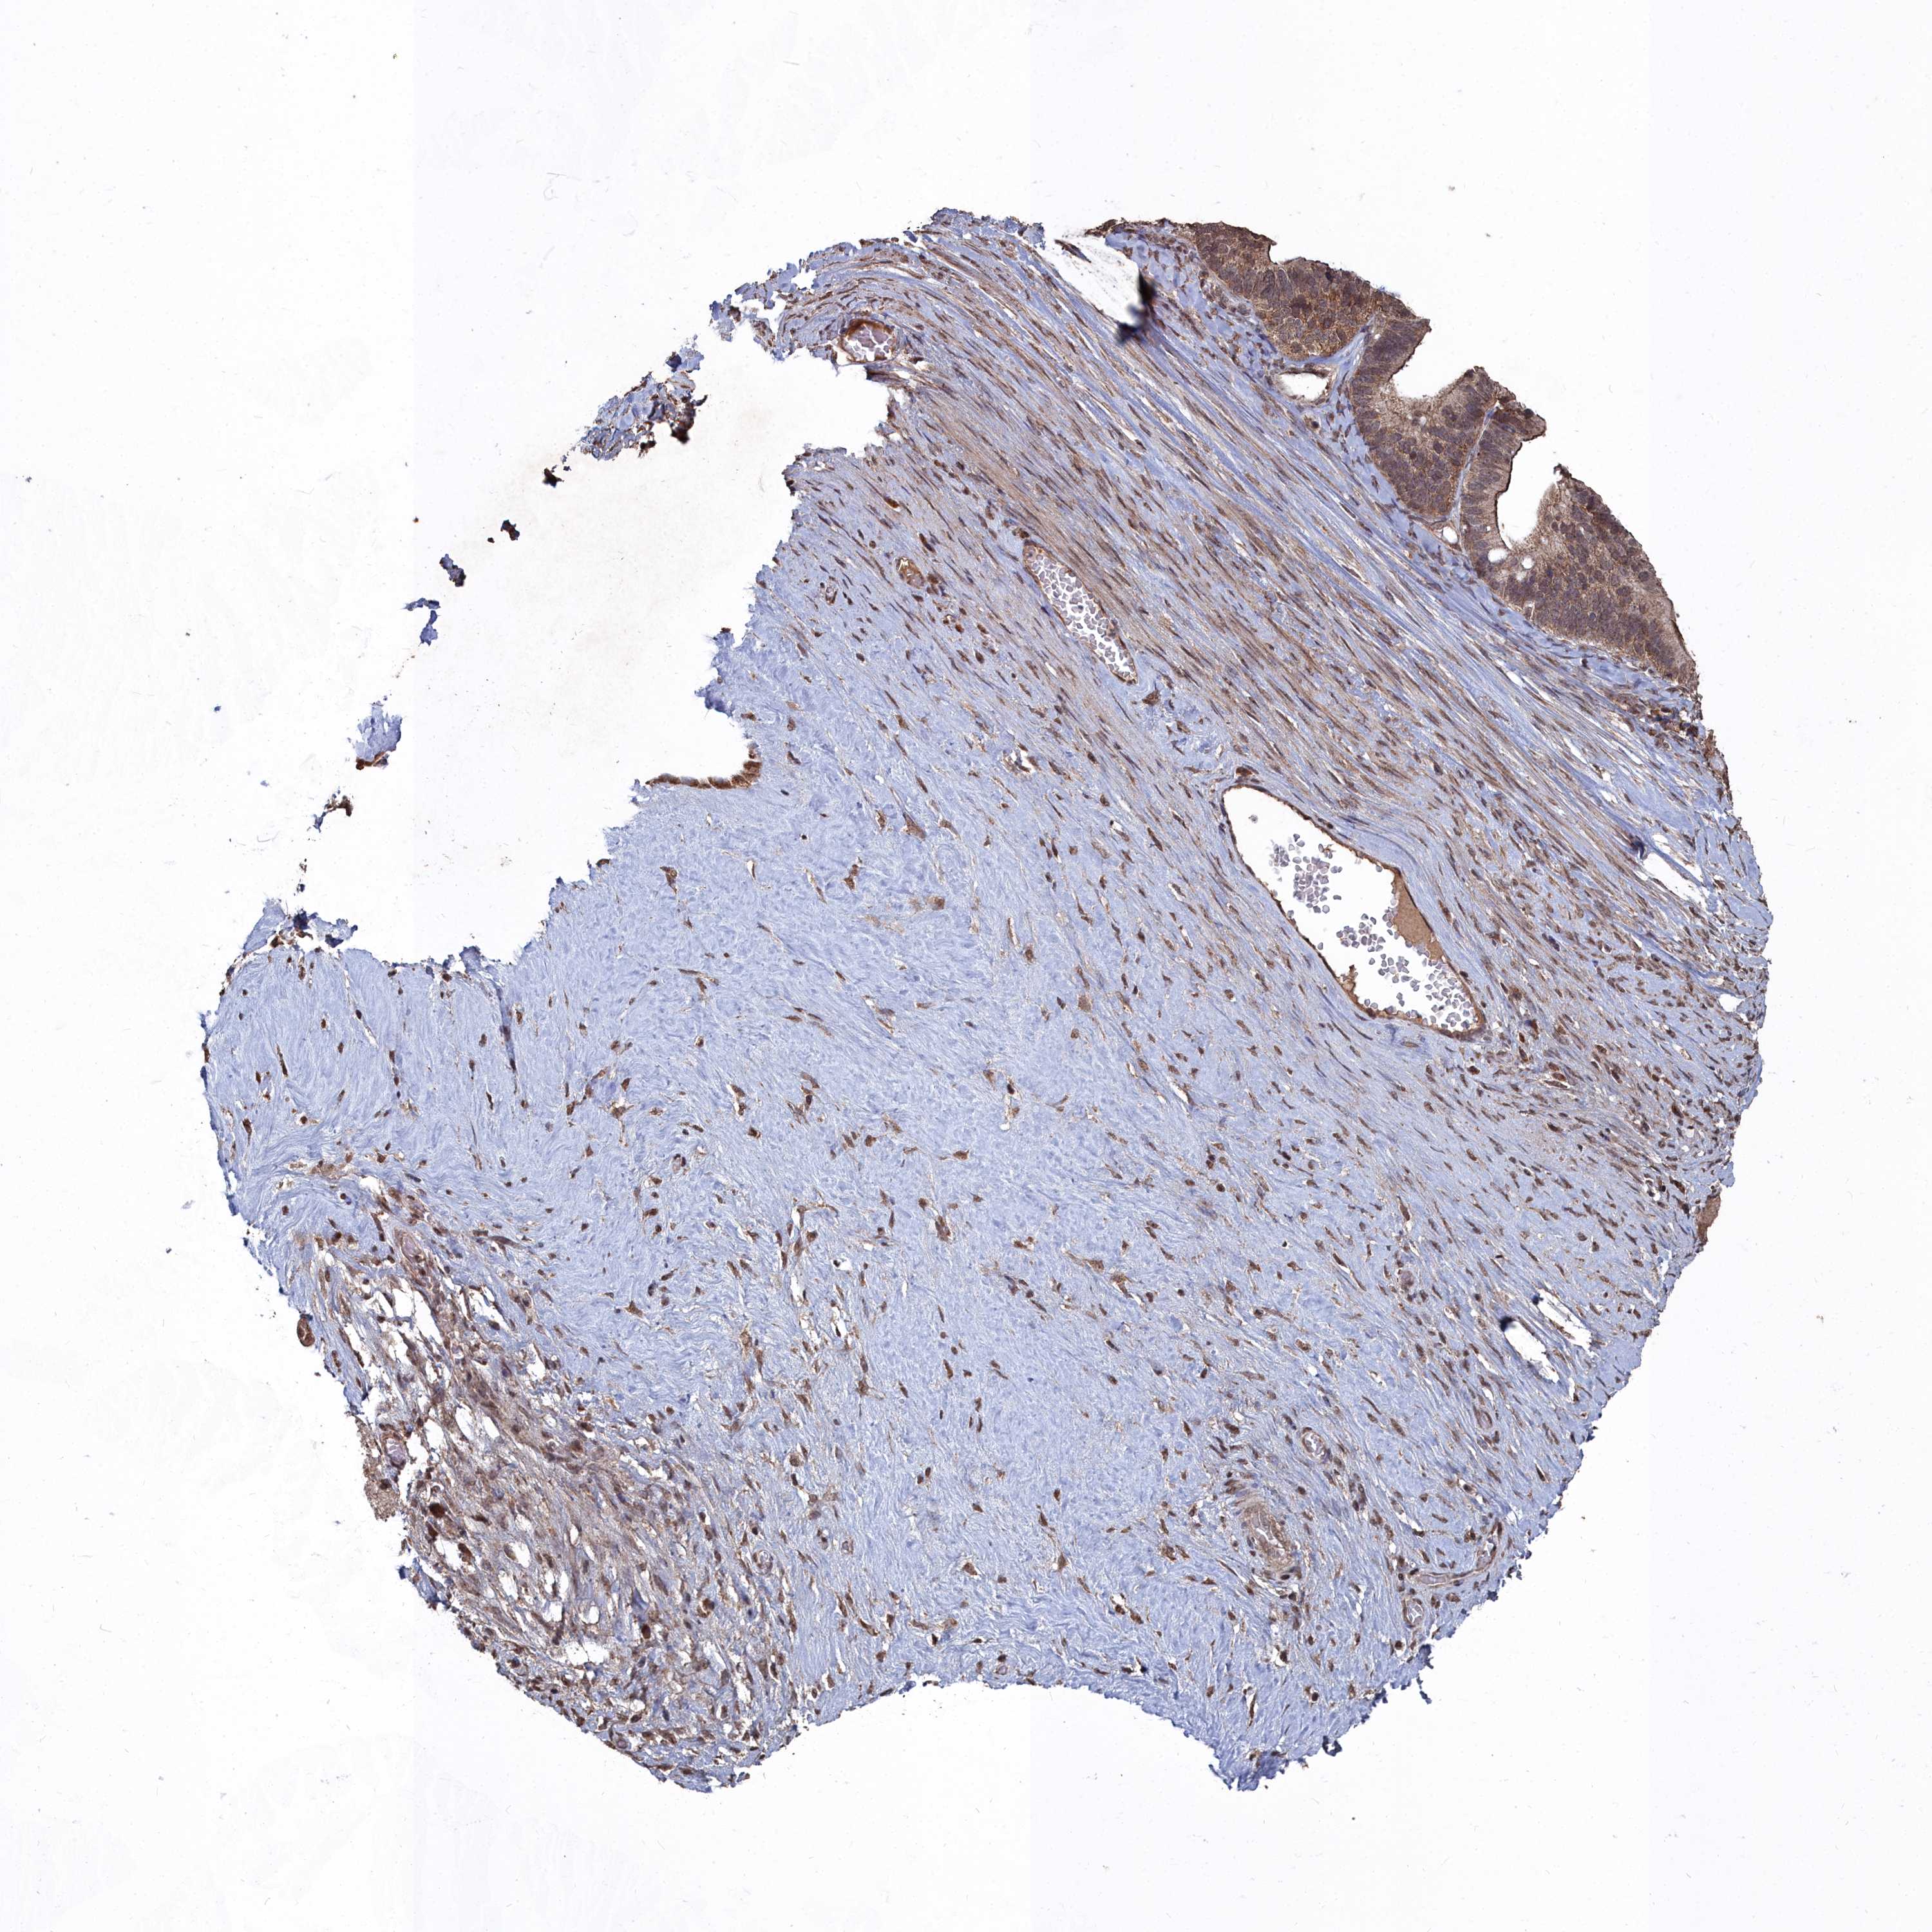

OVARIAN CANCER - Protein expressioni

A mouse-over function shows sample information and annotation data. Click on an image to view it in a full screen mode. Samples can be filtered based on level of antibody staining by selecting one or several of the following categories: high, medium, low and not detected. The assay and annotation is described here.

Note that samples used for immunohistochemistry by the Human Protein Atlas do not correspond to samples in the TCGA dataset.

Antibody stainingi

Antibody staining in the annotated cell types in the current human tissue is reported as not detected, low, medium, or high, based on conventional immunohistochemistry profiling in selected tissues. This score is based on the combination of the staining intensity and fraction of stained cells.

Each image is clickable and will lead to virtual microscopy that enables deeper exploration of all samples and also displays staining intensity scores, fraction scores and subcellular localization as well as patient and tissue information for each sample.

Antibody HPA045615

Staining

High

Medium

Low

Not detected

Intensity

Strong

Moderate

Weak

Negative

Quantity

>75%

75%-25%

<25%

None

Location

Nuclear

Cytoplasmic/membranous

Cytoplasmic/membranous,nuclear

Cystadenocarcinoma, serous, NOS

Carcinoma, NOS

Cystadenocarcinoma, mucinous, NOS

Carcinoma, endometroid